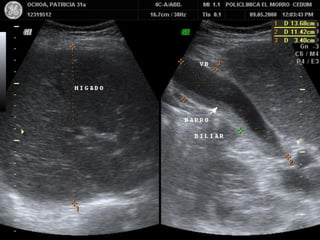

PATOLOGIA BILIAR

BARRO BILIAR

HEMORRAGIA VESICULAR